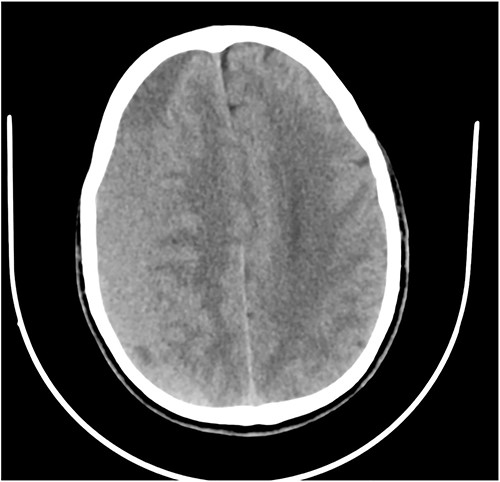

Case 1 – unilateral ptosis

A 42-year-old woman presented to the outpatient clinic with a 2-week history of headaches and 3-day history of drooping of the right eye and inability to open the eye. She had been involved in a passenger road traffic accident 3 weeks prior. At presentation she was fully conscious, and oriented in time, place, and person. However, she had a recent onset painless drooping of the right eyelid (Fig. 1A). Her vision was preserved with dilated pupils that reacted very slowly to light as well ophthalmoplegia. Other cranial nerves were normal on examination. There were no long tract signs.

(A) Pre-op with right ptosis/ophthalmoplegia. (B) Pre-op axial CT showing right CSDH. (C) Post op with resolution of ptosis.

Brain CT scan done revealed a right fronto-temporal CSDH causing uncal compression and midline shift as well as partial effacement of the ipsilateral lateral ventricle (Fig. 1B).

She underwent a right frontal and parietal burr hole drainage of the haematoma under local anaesthesia and sedation. Her post-operative course was satisfactory, and she was discharged on the 4th day post-surgery. She had complete resolution of her symptoms in 2 weeks (Fig. 1C).